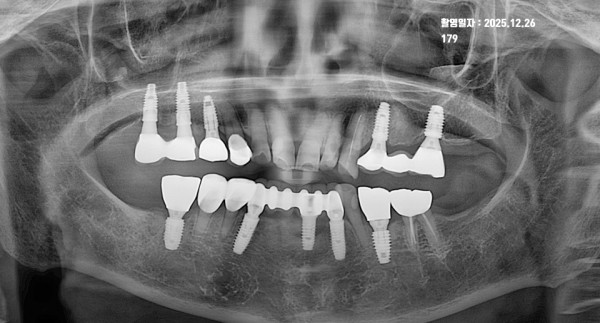

2. 2025년 12월 26일: 11년 경과 후 정기검진 상태

두 번째 사진은 가장 최근인 2025년 12월 26일에 촬영한 정기검진 파노라마입니다. 11년이라는 긴 세월이 지났음에도 불구하고 놀라운 결과를 보여주고 있습니다.

* 치조골 유지의 핵심: 사진을 보시면 2014년과 비교했을 때 임플란트 주변 치조골의 높이 변화가 거의 없습니다. 임플란트 나사선이 밖으로 노출되거나 뼈가 녹아내린 흔적 없이 아주 견고하게 유지되고 있습니다.

* 장기 안정성 확인: 10년이 넘는 시간 동안 저작 기능(씹는 힘)을 완벽히 수행하면서도 주변 조직에 염증이나 골소실이 발생하지 않았다는 것은, 초기 수술의 정확도와 사후 관리가 얼마나 완벽했는지를 증명합니다.

* 추가 진료: 그사이 다른 부위에 추가적인 임플란트 식립이 있었지만, 기존에 심었던 임플란트들이 든든한 버팀목 역할을 해주고 있습니다.